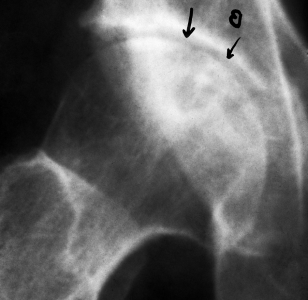

病例2。49岁股骨颈骨折不愈合,采用钢针固定治疗,合并股骨头坏死3年。治疗9个月后骨折愈合,坏死修复。治疗前,股骨颈骨折头部下移,骨折部位可见透光线,两钢针均有明显钉痕,伴发股骨头坏死。治疗后骨折愈合,股骨头坏死修复,骨小梁清晰,钉痕消失。

Case 2. A 49 year old femoral neck fracture was fixed with steel needle for three years. The fracture was healed after 9 months of necrosis. Before the treatment, the head of the femoral neck fracture moved down, the light transmission line was seen at the fracture site, and obvious nail marks were seen on both steel needles. The bone trabecula was clear and the nail mark disappeared. The density of femoral neck fracture repair was uniform after nail removal.